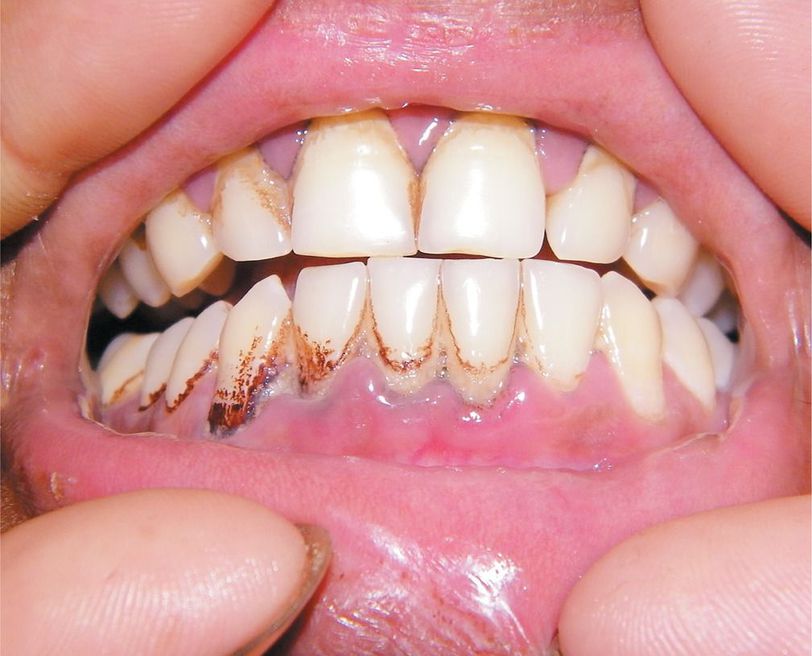

An 18-year-old nonsmoking man presented to the emergency department with a 1-week history of diffuse, colicky abdominal pain. He had had no change in his bowel or bladder function. He had worked in a battery-recycling factory for the past year. Examination revealed diffuse abdominal tenderness, as well as a bluish line around the gums, known as Burton's line. Results of routine hematologic, liver-function, and kidney-function tests were normal. Ultrasonography of the abdomen was unrevealing. The blood lead level was elevated at 81 ng per deciliter (3.9 nmol per liter) (reference range, <10 ng per deciliter [0.5 nmol per liter]). The patient was admitted to the hospital and started on chelation therapy with penicillamine. He was discharged in 2 weeks, after the pain had subsided and the blood lead level had declined; the Burton's line had disappeared. He was counseled regarding potential occupational exposure. In developing countries, occupational exposure is the main cause of lead poisoning. Persons working at sites where batteries or plastics are manufactured, at printing or recycling factories, or in the paint or ceramics industries are at greatest risk. Preventing exposure is the most critical intervention. In developing countries such as India that have a growing recycling industry, education regarding the hazards of heavy-metal poisoning is important.